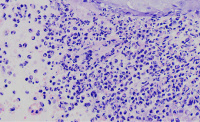

外阴多发赘生物,请教老师们,怎么报告?

性别

女

年龄

62

发现外阴数十粒丘疹样结节,伴溃疡

外阴丘疹样赘生物

灰白色组织两粒0.5*0.3cm

考虑:疱疹病毒感染

疱疹性皮炎。

符合疱疹性皮炎。